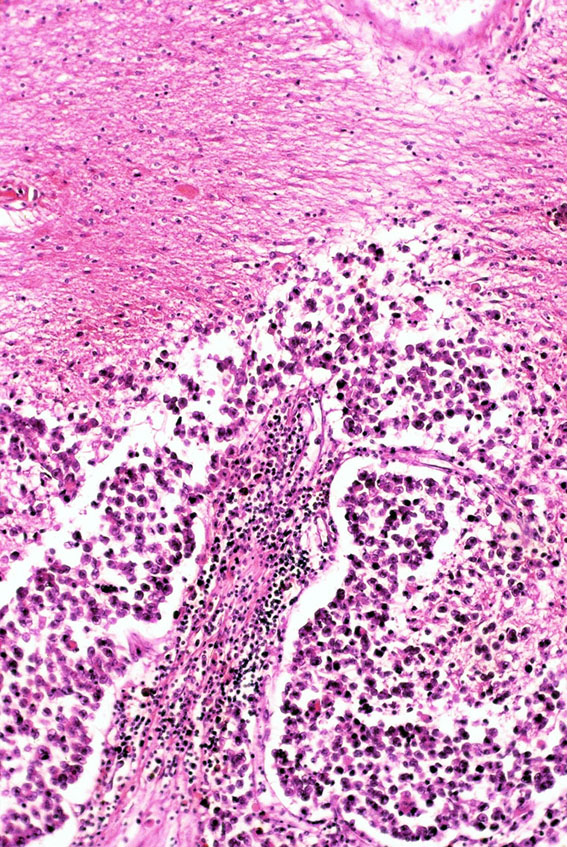

病理診断は困難ではありません。左側の写真のように,多くの場合にHE染色でtwo-cell patternと呼ばれる, 大型の腫瘍細胞と小型のリンパ球 (T cells) 浸潤の特徴的な病理像で診断がつきます。大型の腫瘍細胞は楕円形の大きな核に大きな核小体が特徴です。

弱拡像です。類円形で大型の核を有するgerm cell (胚細胞)類似の細胞と小型のリンパ球からなる腫瘍で、two cell patternと呼ばれています。

大型のgerm cell類似の細胞 (germ cellと呼ぶ)では腫大した核小体が明瞭にみられます(太い矢印)。小型の細胞の中にはplasma cell (細い矢印)も見られます。